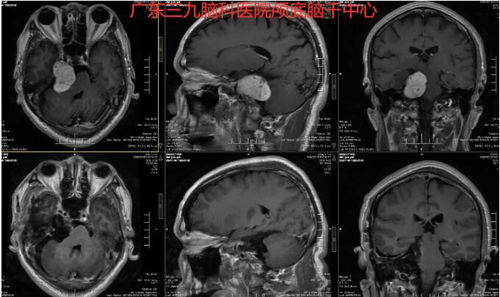

图3:术前术后MR对比示术后改变,肿瘤全切。